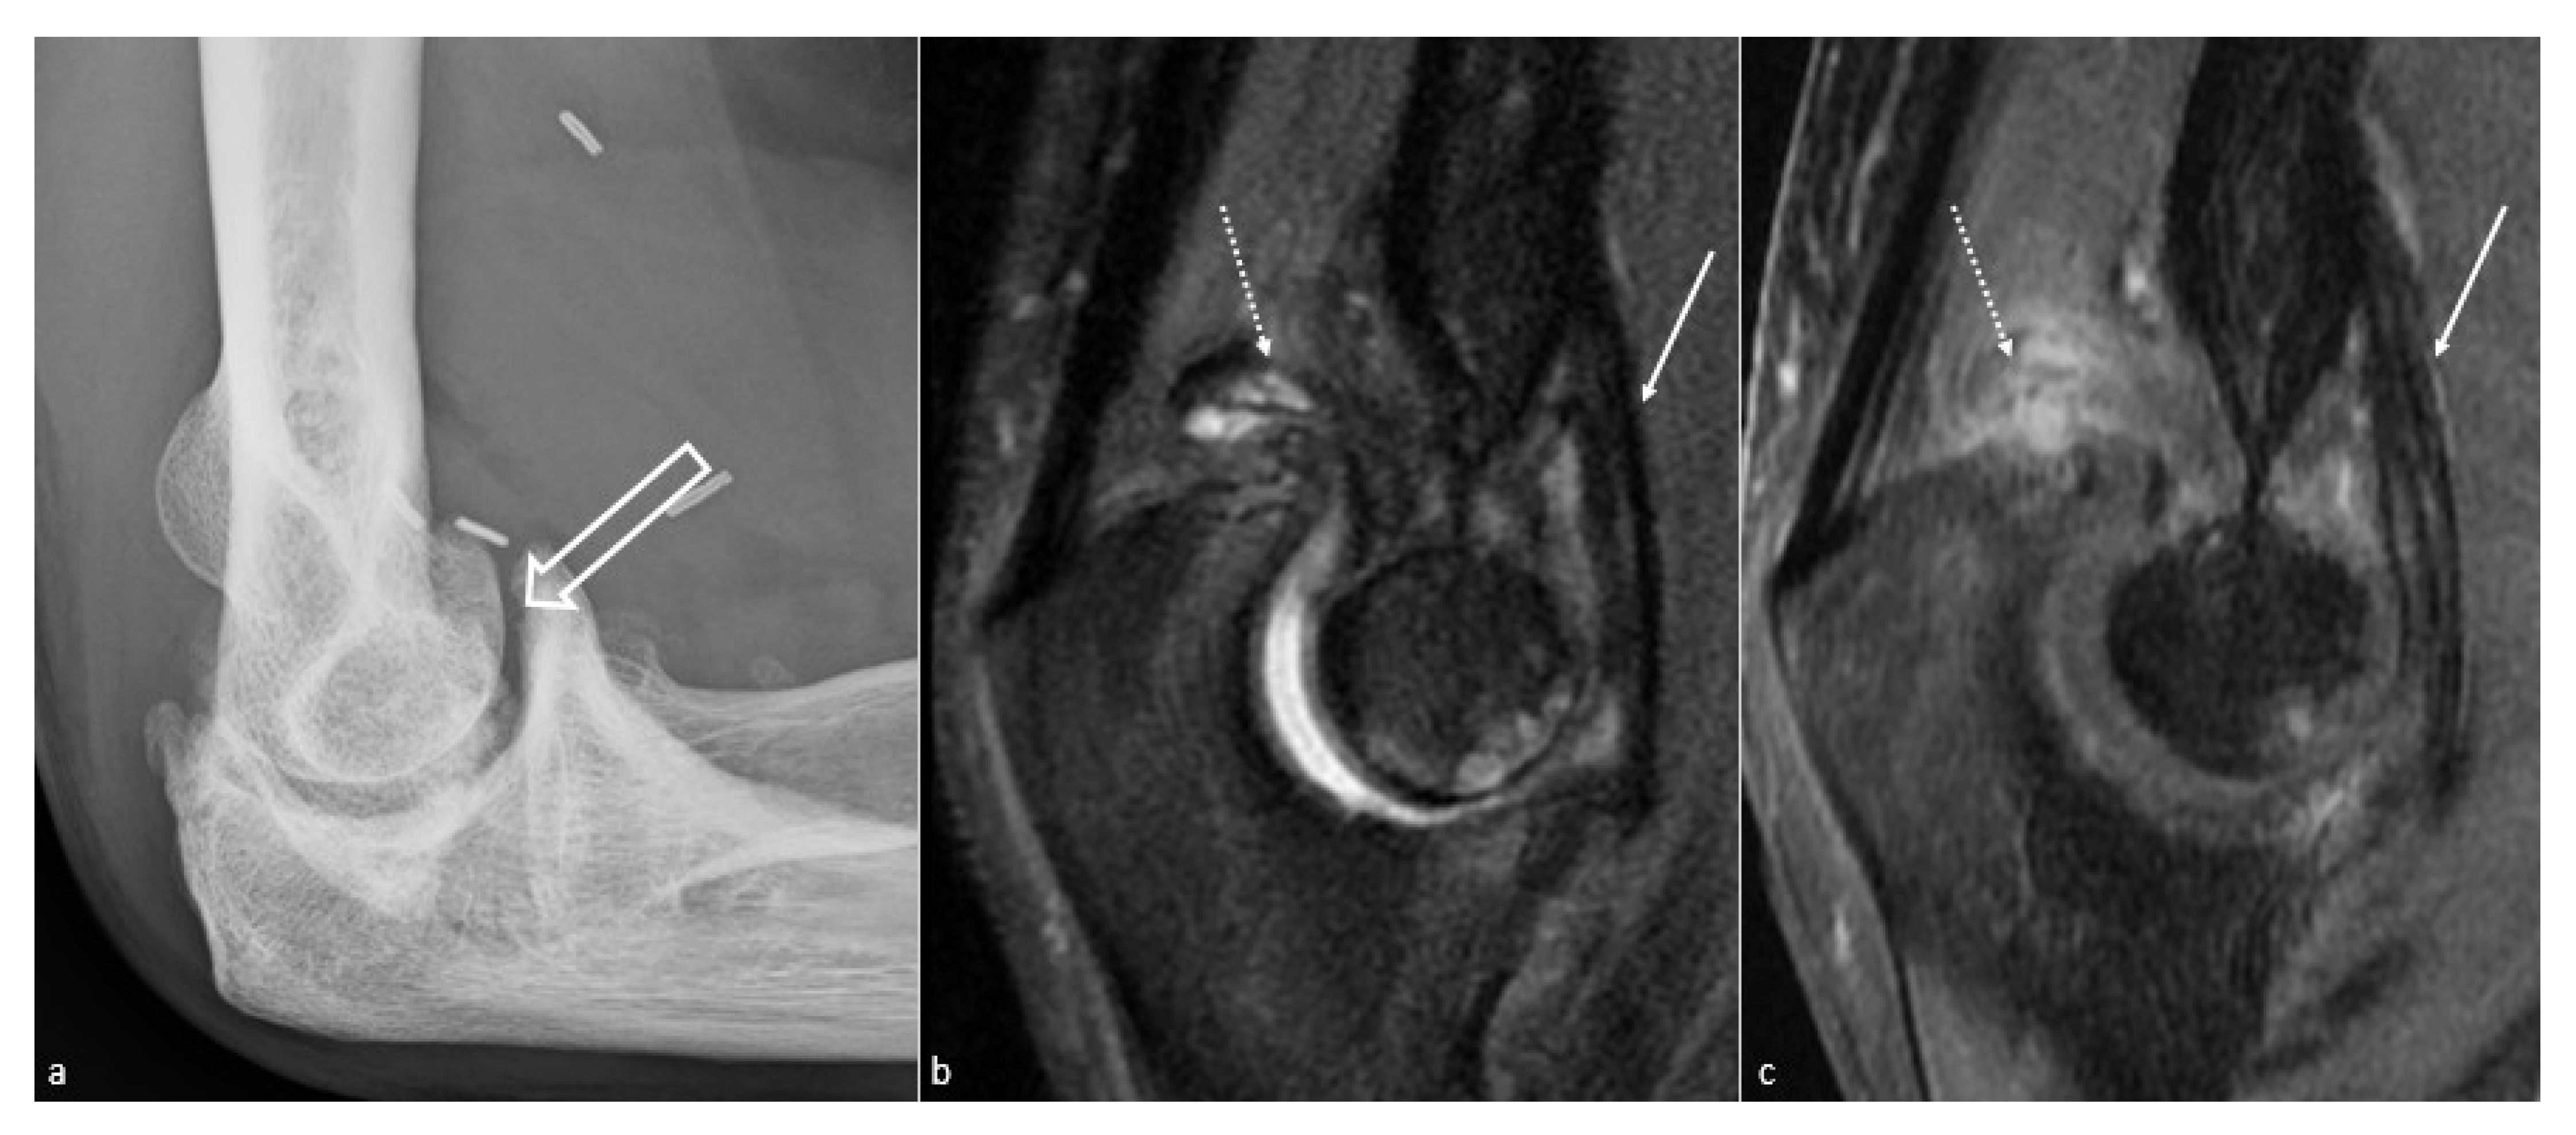

5.1. Conventional Radiographs

5.3. CT and CT Arthrography

5.4. MR Imaging